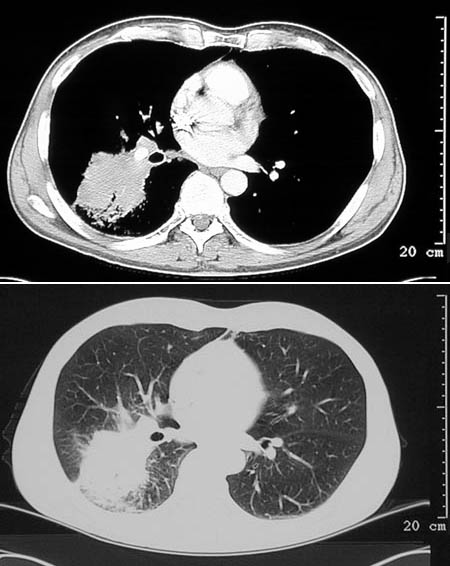

| This chest CT scan in bone window above and lung window below demonstrates an abscess that resembles a tumor mass. Note that this lesion infiltrates to the chest wall. Biopsy revealed Actinomyces israeli infection as the etiology. Both Actinomyces israeli and Nocardia braziliensis are long filamentous bacteria that produce lesions resembling abscesses or fungal granulomas. These organisms are more likely to infect immunocompromised persons. |